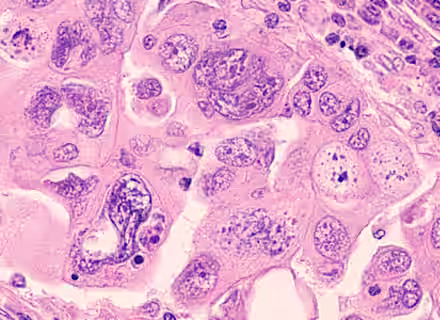

Ovarian cancer generally presents as non-specific abdominal symptoms such as abdominal discomfort and swelling. It may also be associated with urinary frequency or post menopausal bleeding.  More advanced disease may present with loss of appetite or weight loss.

Diagnosis should be reached by clinical examination of the abdominal mass, followed by investigations to include full blood count, chest x-ray, pelvic ultrasound and an abdominal/pelvic CT scan together with measurement of serum levels of CA-125 (a marker for ovarian cancer).

If ovarian cancer is diagnosed early the chance of being cured is normally good. Treatment for ovarian cancer depends on the staging. If the tumour is confined to one ovary, surgery alone may be sufficient.  If the tumour is more advanced, chemotherapy may also be indicated.